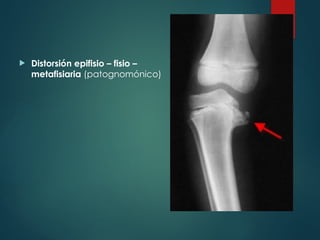

 Distorsión epifisio – fisio –

metafisiaria (patognomónico)

Clínica  Habitualmente asintomático Ex Físico - Genu varo exacerbado al pararse en un pie - Prominencia palpable en borde medial de la metáfisis proximal de la tibia - Torsión tibia interna - Bilateral 50%

• 67.

 Distorsión epifisio– fisio – metafisiaria (patognomónico)